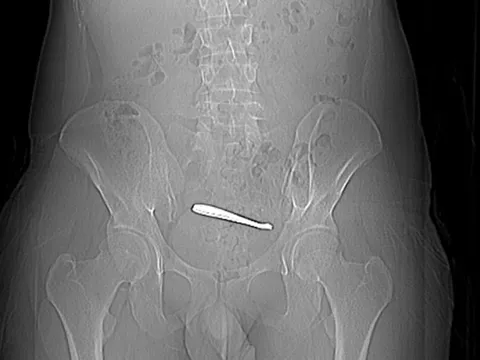

Người đàn ông đau bụng suốt 1 tuần, bác sĩ kiểm tra thì sốc nặng

Sau gần một giờ phẫu thuật, các bác sĩ đã lấy thành công cả hai chiếc thìa ra khỏi bụng người đàn ông.